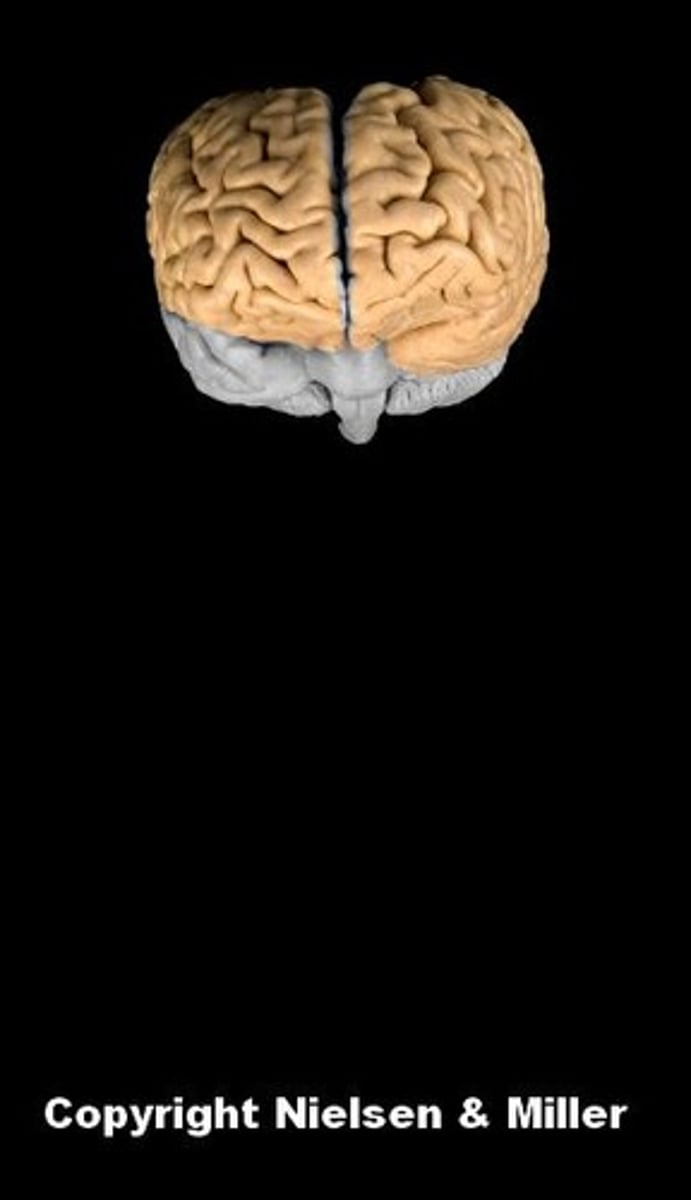

brain

cerebral hemispheres

cerebrum